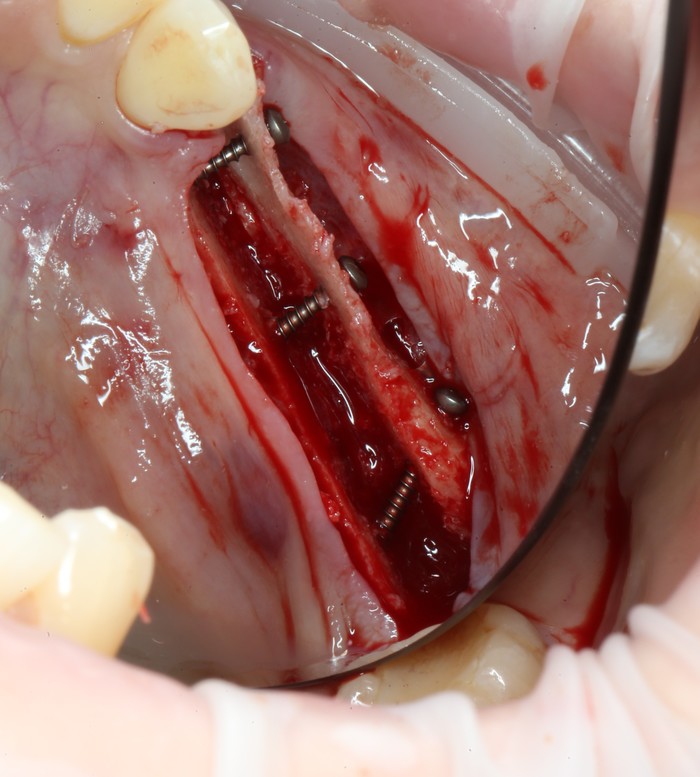

Уже на следующий день была запланирована имплантация.

Дабы не перегружать вас обилием одинаковых картинок, я оставлю один рентгеновский снимок, но отмечу, что установка имплантатов на верхней и нижней челюсти проводилась с разницей в 10 дней.

На верхней челюсти было дополнительно удалено два боковых резца с одномоментной установкой имплантатов, так же они были установлены в области четверок и шестых зубов. Дополнительно было проведено наращивание костной ткани - двусторонний синус - лифтинг. О том, что это такое, можно почитать ТУТ и ТУТ.

После нехитрых манипуляций мы прощаемся с Русланом на 4 месяца.

Этого времени достаточно на приживление имплантатов.